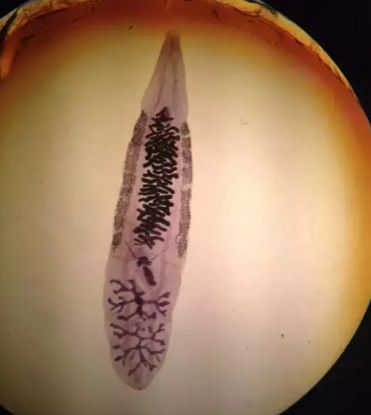

19.华枝睾吸虫

华支睾吸虫体形狭长,背腹扁平, 前端稍窄,后端钝圆,状似葵花子,体表无棘。虫成虫寄生于人体的肝胆管内。